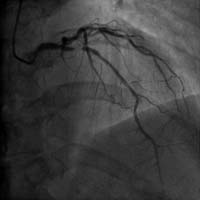

介入手術治療嚴重冠心病